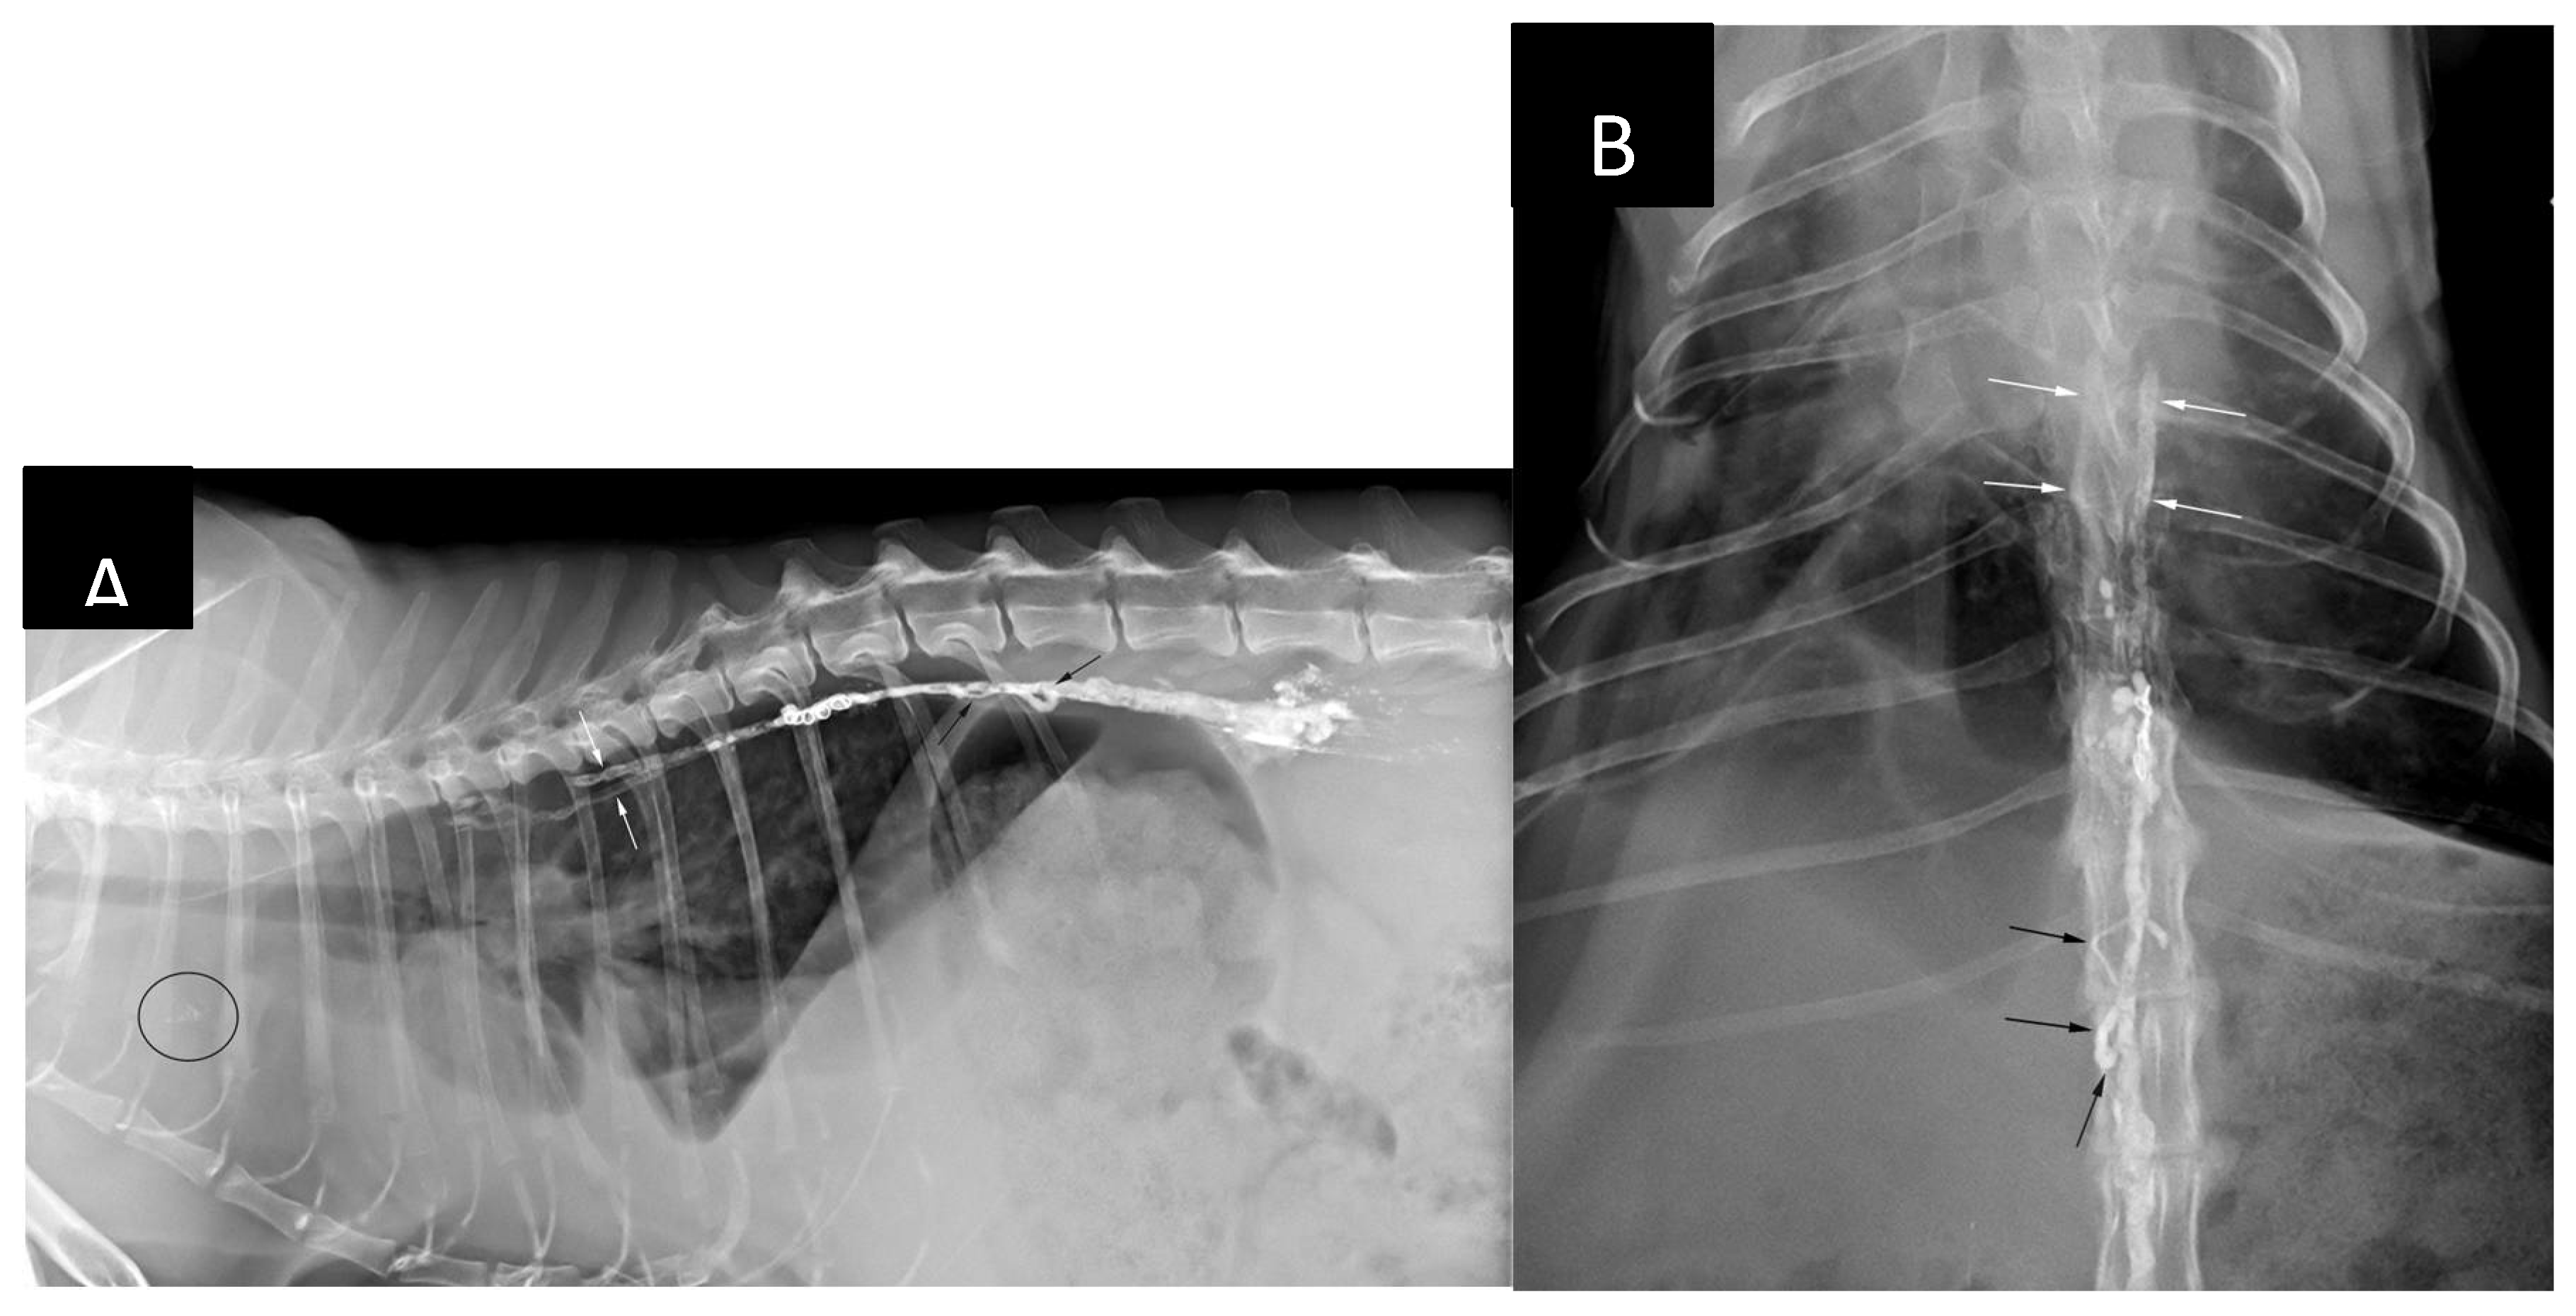

The patient was placed in sternal recumbency for intrametatarsal pad injection of iohexol (Omnipaque 300 mg I / ml, GE Healthcare), 1.0 ml/kg divided in two sites (0.5 ml/kg/site), as described by Chiang et al. [14]. Following the injection and gentle massage of the pads the patient was positioned in left lateral recumbency and draped for right lateral sublumbar approach to the cisterna chyli (Figure 3). The contrast injection resulted in strong opacification of the lymphatics up to the level of the caudal lumbar vertebrae, however, the opacification was progressively less intense further cranially. By the time all the equipment was set up for CC puncture there was nearly no visible contrast within the CC (Figure 3).

Figure 3. Fluoroscopy images obtained after bilateral intrametatarsal pad iohexol injection. (A) Opacification of the lymphatics is clearly visible up to the level of the caudal lumbar spine (black arrow) 2 minutes after the injection. (B) Opacification of the cisterna chyli (black arrowheads) can be seen at 14 minutes post-injection. (C) Fluoroscopy image taken immediately before ultrasound-guided access at 16 minutes post-injection (2 minutes after the image B had been taken). The opacification of the CC can no longer be appreciated.